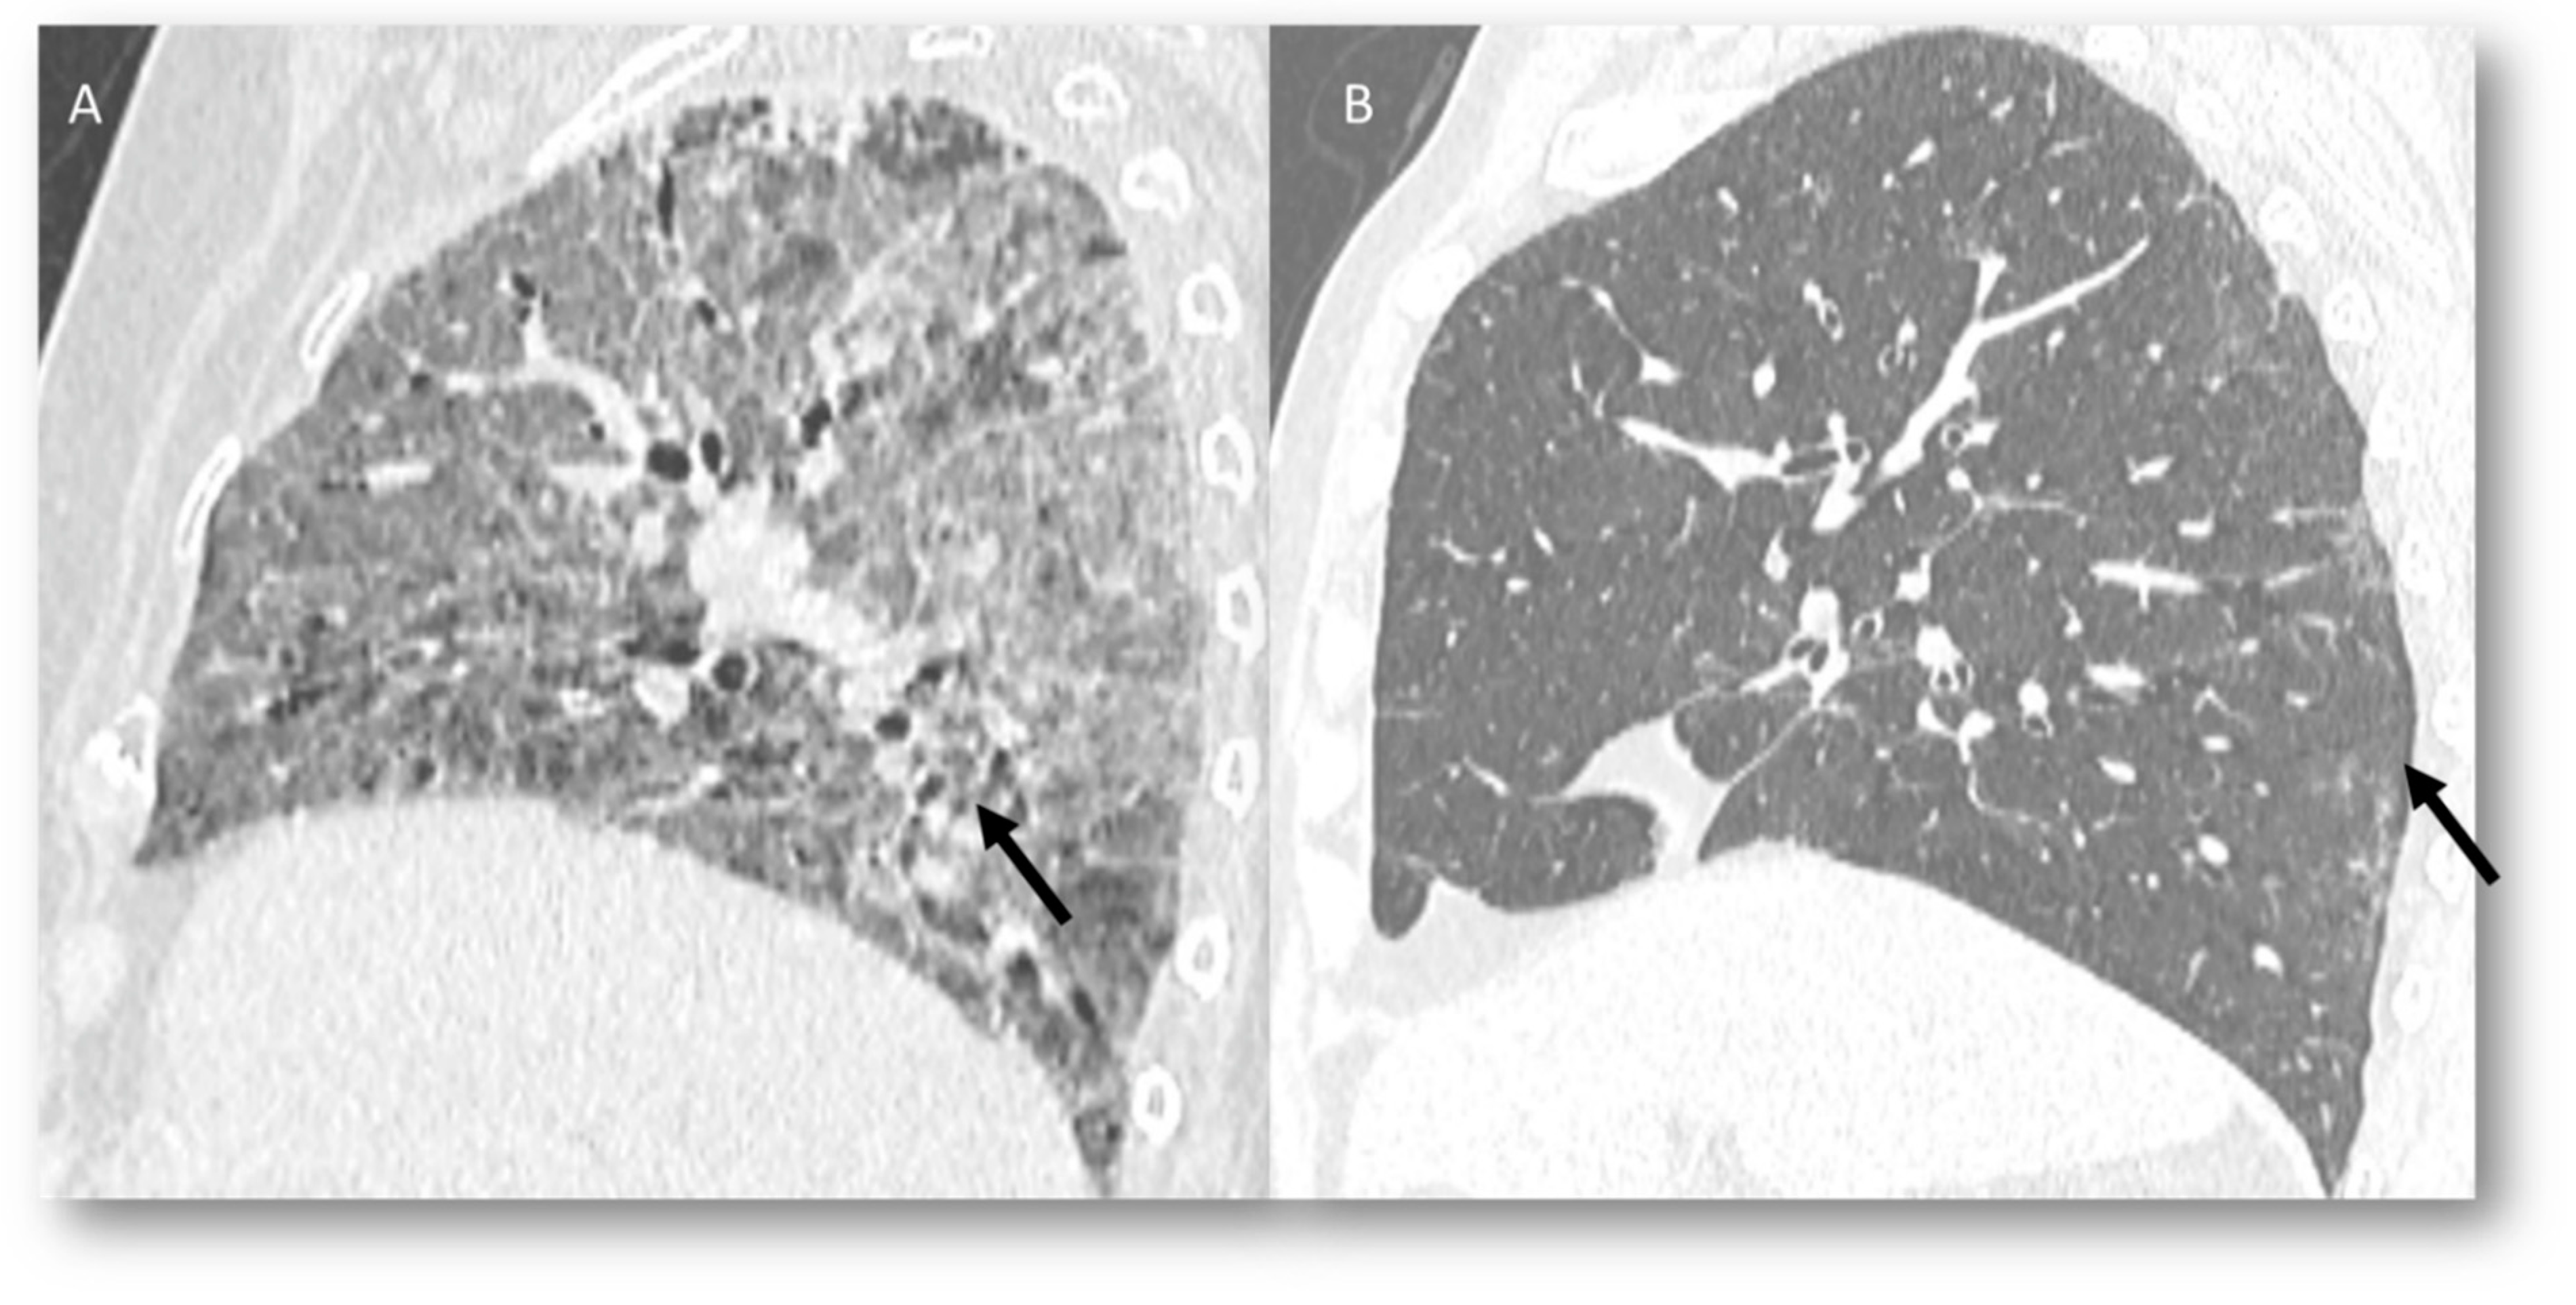

3.3. Radiation Pneumonia

| RP | Target area | Ground-glass opacities and consolidative opacities. | Direct damage to the DNA and indirect damage through the production of reactive oxygen species (ROS), causing changes in vascularity and capillary permeability, activation of the inflammatory response and alteration of immunological response |